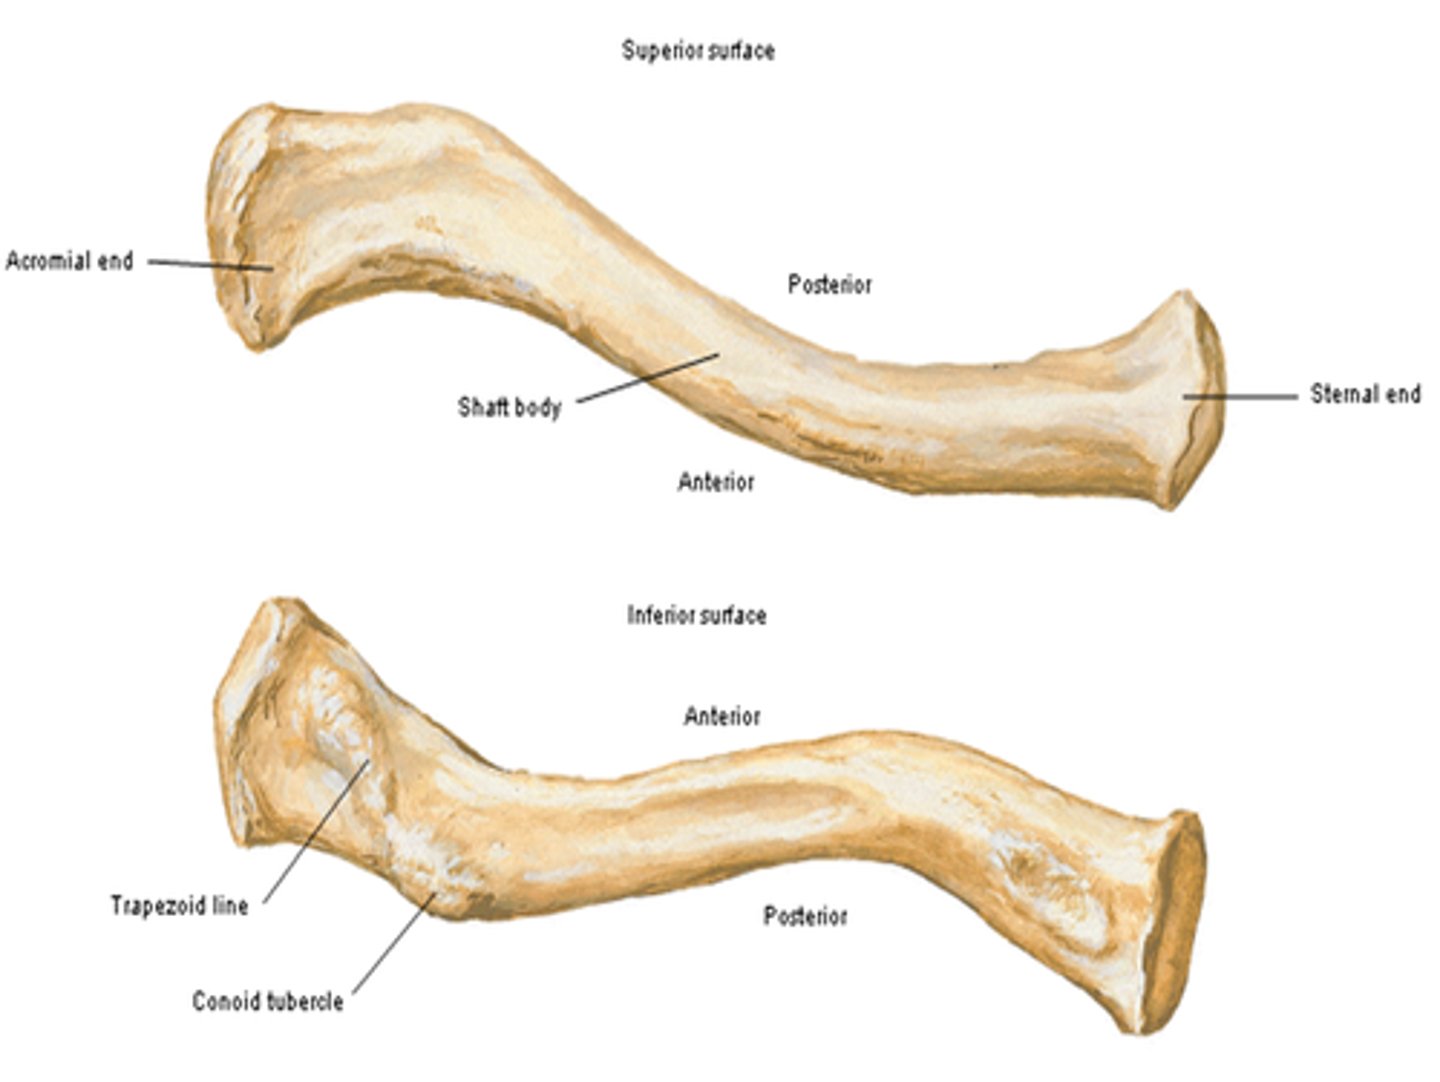

Parts of the clavicle:

- shaft

- superior surface

- inferior surface

Shaft of the clavicle:

double curved in the horizontal plane, which increases resilience

Middle half of the shaft of the clavicle:

convex anteriorly, and lateral half concave anteriorly

Sternal end of the shaft of the clavicle articulates:

articulates with manubrium via the sternoclavicular joint

Acromial end of the shaft of the clavicle articulates:

articulates with acromion via acromioclavicular joint

Location of superior surface of the clavicle:

lies deep to the platysma muscle and skin and it is smooth

Inferior surface of the clavicle:

rough surface with ligaments binding to it

Location of conoid tubercle of the inferior surface of the clavicle:

near acromial end of clavicle

Function of conoid tubercle on the inferior surface of the clavicle:

support for the medial part of the coracoclavicular ligament

Location of the trapezoid line of the inferior surface of the clavicle:

nearer to the acromial end than the conoid tubercle

Function of the trapezoid line of the inferior surface of the clavicle:

support for the lateral part of the coracoclavicular joint